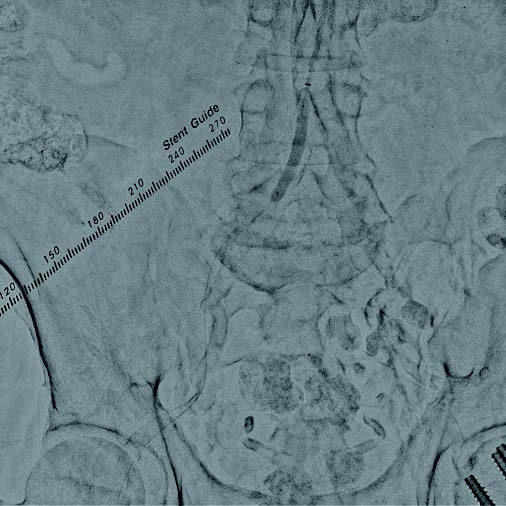

術前造影画像

本症例は総大腿動脈からの順行性穿刺による右膝下動脈の治療を予定していることから、上腕動脈穿刺による腸骨動脈へのEVTを計画した。右上腕動脈から6 Frガイディングシースを用いてアプローチし、術前の下肢血管造影を行った。重症下肢虚血患者であり、安定したinflowの確保が重要と考え、高度石灰化を伴うことおよび血管径が11 mmと大きいことを踏まえ、後拡張の汎用性の高いVBX ステントグラフトを選択する方針とした。0.014 inchガイドワイヤーで病変通過後、6.0 × 40 mmバルーンで前拡張を行った(図1)。ガイドワイヤーを0.035 inchスティッフタイプに変更し、VBX ステントグラフト7 × 39 mmを後拡張での短縮を考慮し、数 mm 程度大動脈に突出させる形で留置した(図 2)。10.0 × 40 mmバルーンで後拡張(図3)を行い、IVUSで解離等がないことを確認し、最終造影で合併症が無いことを確認し手技を終了した。